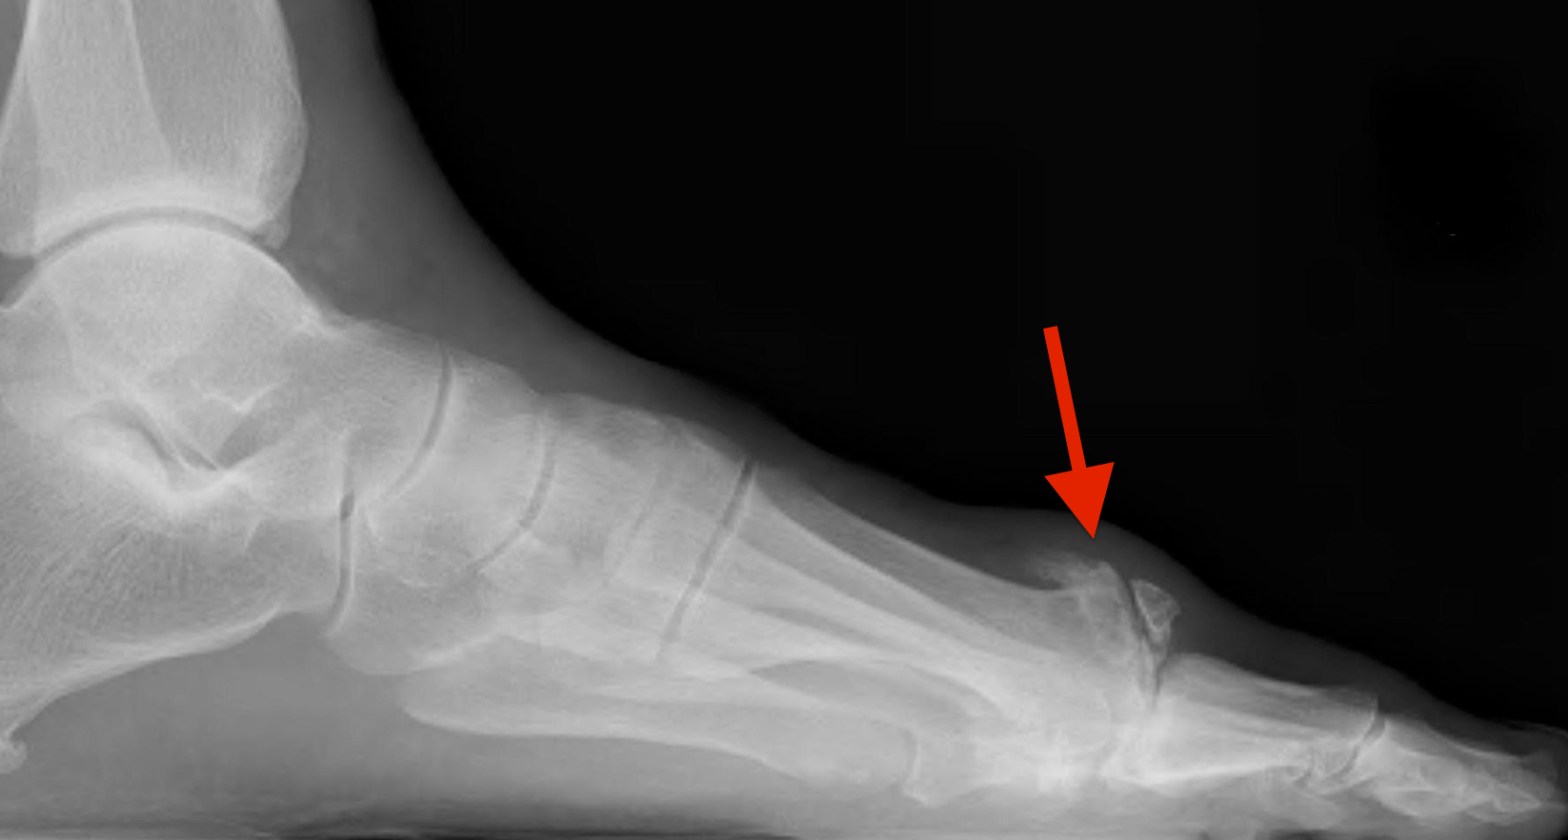

What causes the bump on top of my big toe joint?

In this post I will discuss the ‘bump’ some people have on top of their big toe joint. Many people are aware of the bump some people have along side of the big toe joint, as it goes by the name of a ‘bunion’. What is less known is the cause and treatment of aContinue reading “What causes the bump on top of my big toe joint?”